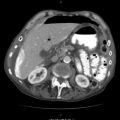

Fig. 37.2

CT angiogram confirming a large mediastinal haematoma